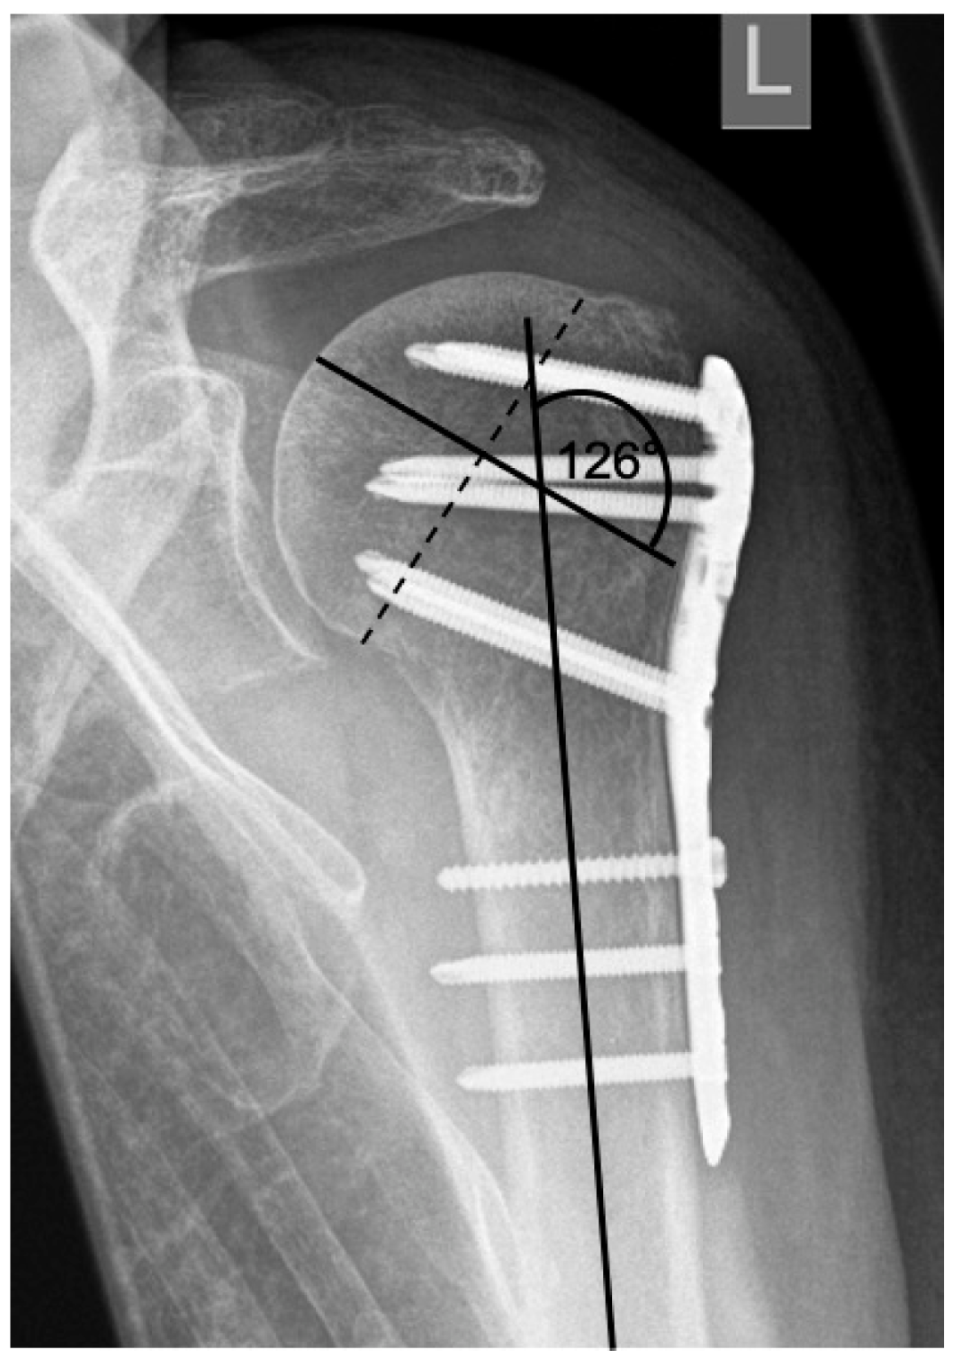

| 1 | ![]() | Complication Type 1 is defined by a mild, stable varus or valgus displacement (<20°) of the humeral head without resulting in a screw cutout through the humeral head cortex. |